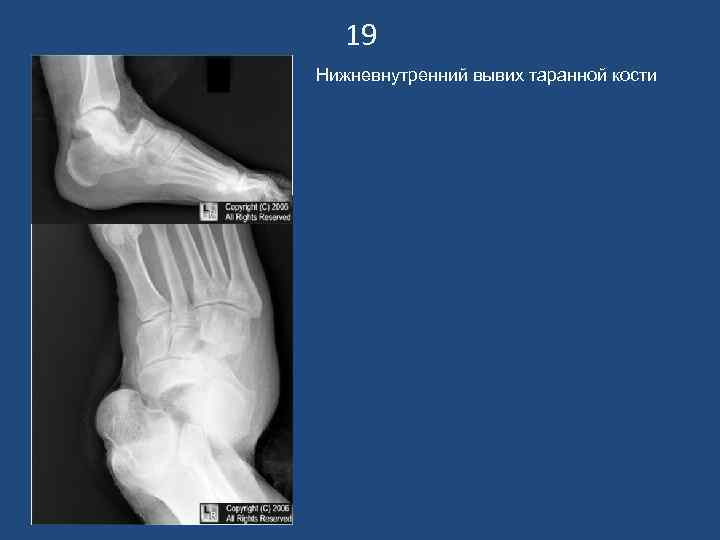

19 Нижневнутренний вывих таранной кости